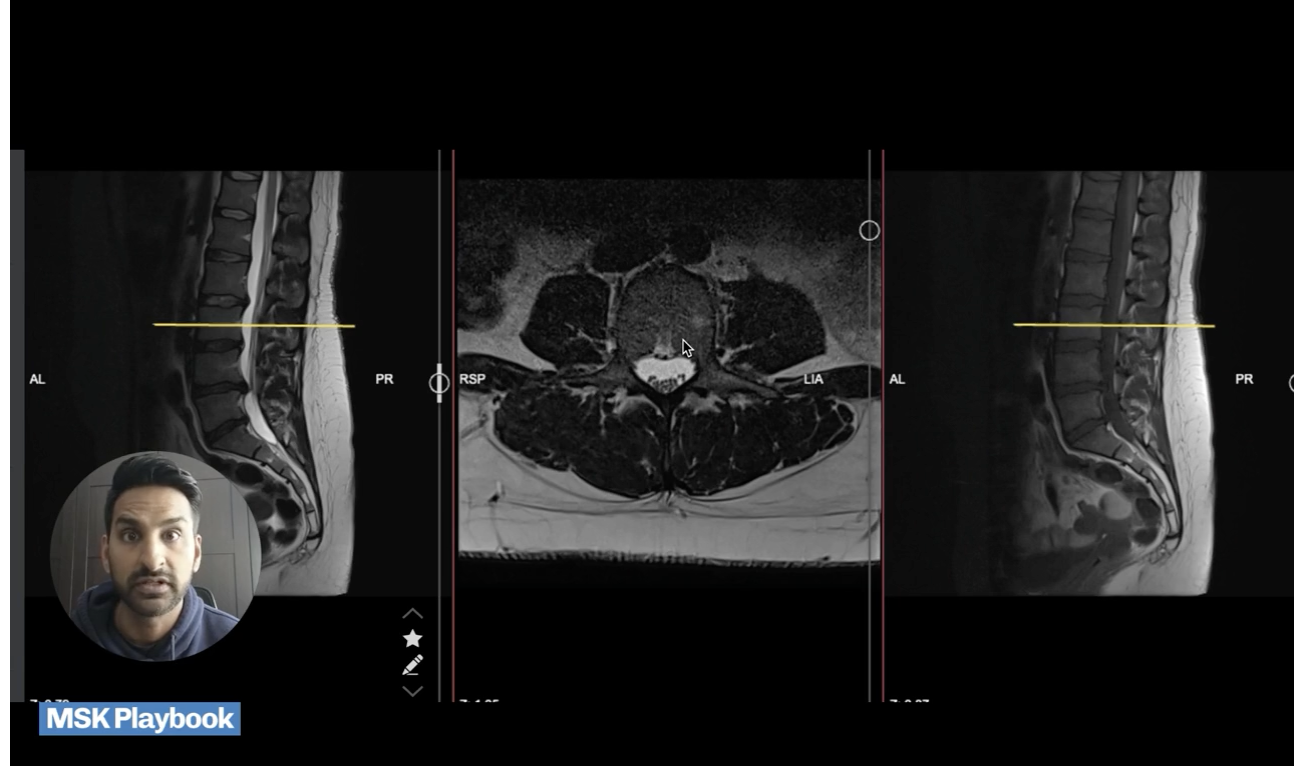

5.1 – MRI of the spine – Live MRI tutorial to walk you through the key anatomy,  how to identify common pathology and explain the scan to your patient!

5.2 MSK imaging series – (Sports trauma, fractures, OA, Ankylosing Spondylitis, Sciatica, Disc disease)

5.3 - MRI of the spine– Learn the key views to be able to show your patient